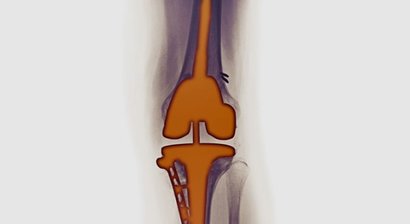

Im Falle einer notwendigen Operation wird diese von mir im Evangelischen Krankenhaus Wien durchgeführt. Meine chirurgischen Schwerpunkte liegen im künstlichen Gelenkersatz , in der Fußchirurgie und den arthroskopischen Operationstechniken.

Ich habe mich auf die Implantation von künstlichen Knie- und Hüftgelenken spezialisiert und setze hier auf monderne minimalinvasive und schonende Operationstechniken (AMIS-Methode).

Künstliches Kniegelenk